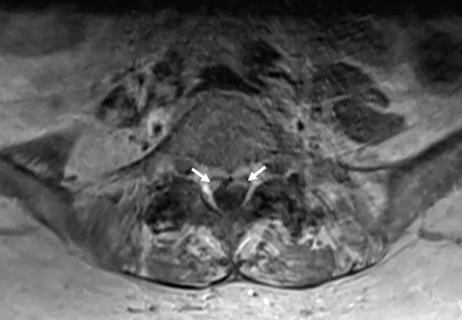

September 28, 2018/Neurosciences/Case Study

Multimodality Evaluation Enables Epilepsy Control in a Patient with Periventricular Nodular Heterotopias

Resulting localization of a single focus paves way for laser ablation